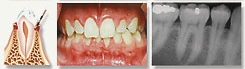

• Gum Disease Therapy – Periodontal

Gingivits